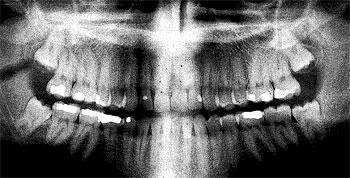

I’m all set for an appointment with the local oral surgeon, Dr. Tidstrom. I have been told by various dentists since 1998 that I need to get my wisdom teeth out. X-rays do in fact show that all four wisdom teeth are growing in. The ones on bottom look like they’re fine, but the two on top literally have nowhere to go, as you can see on the x-ray.